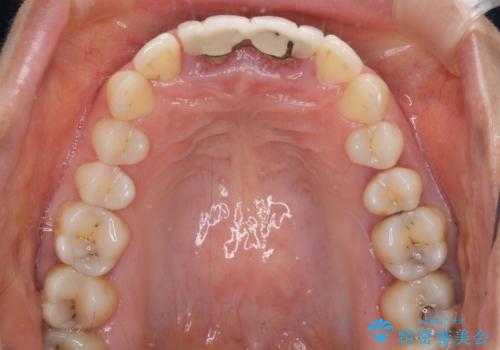

初めは前歯のみの処置で改善を希望されていたため、広範囲に処置範囲を広げることで歯の幅がバランスする治療を提案しましたが、削らなければならない歯が増えてしまうため、患者様と相談して全顎矯正により前歯のスペースを閉じていくこととしました。

不適合なクラウンが装着されていたため、歯周ポケットが深くなっていましたので、矯正治療前に歯周外科処置を行って歯周ポケットを除去し、矯正治療後にオールセラミッククラウンにて補綴治療を行うこととしました。

前歯の見た目はもちろん、出血や腫脹のない健全な前歯の状態を獲得することができました。